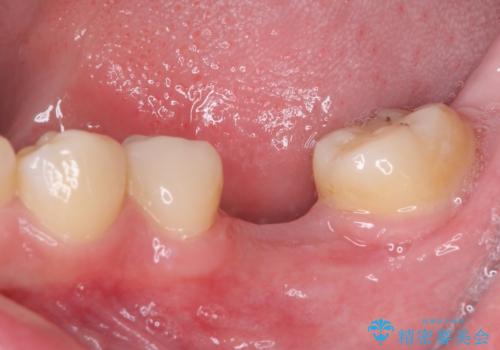

虫歯と抜いたままの奥歯とデコボコの前歯 総合歯科治療

- 放置した虫歯や抜いたままの奥歯、前歯のデコボコを気にして来院された患者様です。

口元の突出感は少なく、下顎の叢生は軽微なものであったので、叢生の強い上顎左右の小臼歯を1本ずつ抜歯し、ワイヤー装置にて矯正治療を行うこととしました。

矯正治療を行う前に、根管治療の必要な上顎前歯と下顎大臼歯の根管治療を行い、矯正治療の途中で下顎の欠損部にインプラント埋入することとし、矯正治療後に補綴治療を行うこととしました。

矯正治療中にインプラント埋入を行うなど、余計な時間や無駄のない治療を行うことができました。